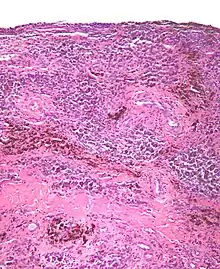

Histopathology of localized TGCT arising in hand finger. H&E stain.

Localized TGCT is sometimes referred to as localized pigmented villonodular synovitis (L-PVNS), giant cell tumor of the tendon sheath (GCT-TS), nodular tenosynovitis, localized nodular tenosynovitis, and L-TGCT.[1]:1[2]:100

The localized form of TGCT is more common.[2]:100[3]:245 Localized TGCT tumors are typically 0.5 cm-4 cm),[2]:101 develop over years,[2]:100 are benign and non-destructive to the surrounding tissue, and may reoccur in the affected area.[2]:101 The most common symptom is painless swelling.[2]:101 Localized TGCT most often occurs in fingers, but can also occur in other joints.[2][5]